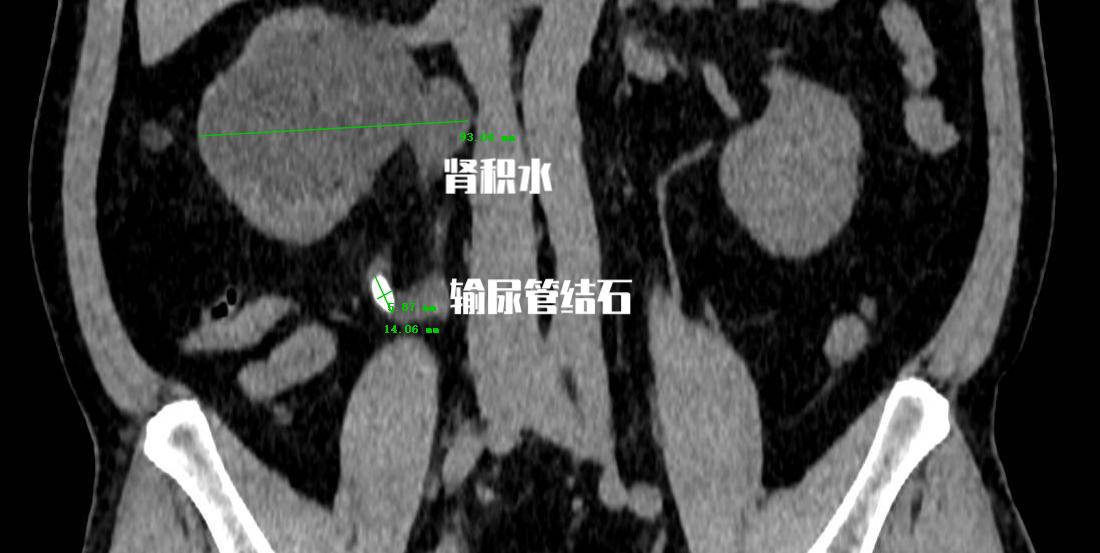

最近我们床位上遇到了一个 “老大难”患者 ,为什么说他是“老大难”呢?因为他有一颗输尿管结石, CT检查提示:左侧输尿管末端结石,结石直径4.84mm 。对于他的结石情况来说,的确最合适的 首选治疗方式就是通过药物的保守治疗方式 。但是一周下来,伴随着间断性的疼痛,在复查的时候发现结石并没有丝毫移动。

首先需要明确一点的是, 输尿管并不会自己长结石 。我们临床上最为多见的输尿管结石其实是肾结石掉落到输尿管以后换了一个名字而已。其实他的前身就是肾结石!

输尿管结石非常常见, 每11个人中就有1人患有泌尿系统结石疾病,并且更严重的问题在于,终生复发率约为50%。 输尿管结石常伴有明显症状,如肾绞痛和血尿。这也是为什么输尿管结石才会引起患者的高度重视的原因。因为疼痛让他们无法忍受!